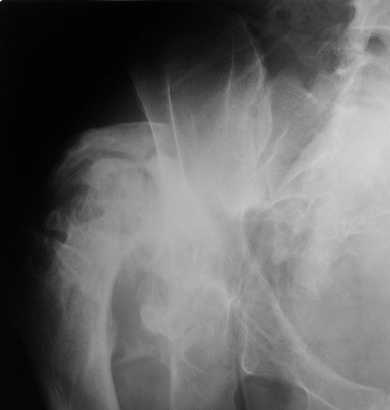

Уважаемые коллеги. Пациент 30 лет 3 года назад в результате травмы получил травматический дефект нижних конечностей до в/3 голеней, был пропущен вывих бедра.

В настоящее время очень неплохо ходит на протезах, движения в неоартрозе близки по объему к здоровой стороне. Основная жалоба - выраженная боль при ходьбе. планируем двухэтапное эндопротезирование - задним доступом мобилизовать проксимальный отдел бедра, резецировать шейку, аппаратом низвести бедро(головку оставить там где она есть, так как больших дефектов не видно(может пригодится в последующем?)). Вторым этапом бесцементное эндопротезирование. Насколько такой вариант реалистичен? Доступ для второго этапа? Может быть другие варианты?С уважением, Максим

Низводить надо обязательно, лучше в аппарате и лучше без остеотомии.

Если в аппарате низводиться не будет, то из небольшого доступа, лучше под контролем С-дуги выполнить остеотомию шейки. Без предварительного

низведения максимально возможная коррекция длины - 2,5-3 см.

Доступ - по предпочтениям хирурга, я предпочитаю передний с расширенной задней мобилизацией.

Решение по ВВ придется принимать по месту.... Сумеете "подрыться" и получить хорошее покрытие чашки (+2 винта об-но) - хорошо, если нет -

костная аутопластика из головки.